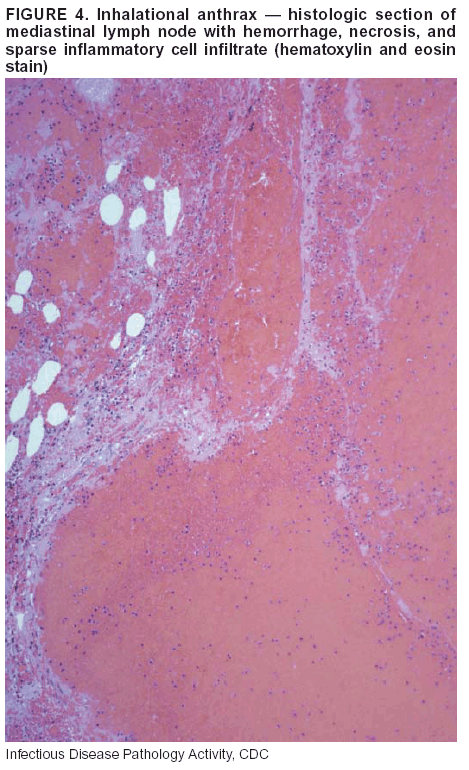

Pathologic Findings. Anthrax has three pathologic forms. Cutaneous anthrax is characterized by an eschar that forms where the bacteria entered the skin (Figure 2). Microscopically, the epidermis has necrosis and crusts, whereas the dermis demonstrates necrosis, edema, hemorrhage, perivascular inflammation, and vasculitis. The lymph nodes that drain the skin site eventually become enlarged, necrotic, and hemorrhagic. Gastrointestinal anthrax is distinguishable by hemorrhagic ulcers in the terminal ileum and caecum accompanied by mesenteric hemorrhagic lymphadenitis and peritonitis. Inhalational anthrax is characterized by hemorrhagic mediastinal lymphadenitis (Figure 3) accompanied by pleural effusions. Histologically, lymph nodes have abundant edema, hemorrhage, and necrosis with limited inflammatory infiltrate (Figure 4) (18,25--29). As any of the three anthrax forms progresses, the bacteria can spread to abdominal organs, producing petechial hemorrhages, and to the central nervous system, producing hemorrhagic meningitis (i.e., cardinal's cap) (Figure 5).

Diagnostic Specimens. Performing a complete autopsy with histologic sampling of multiple organs will help determine the distribution of bacilli and the portal of entry. The specimens that harbor the highest number of B. anthracis organisms vary by the pathologic form of anthrax. For example, diagnosis of cutaneous anthrax requires skin samples from the center and periphery of the eschar, whereas for inhalational anthrax, pleural fluid cell blocks, pleura tissue, and mediastinal lymph nodes have the highest amounts of bacilli and antigens.